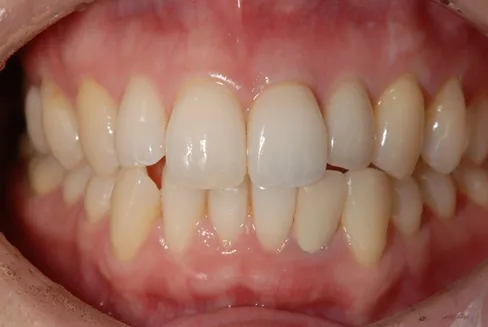

治療完了時

| 患者様のお悩み | 外傷で歯が抜けた |

|---|---|

| 治療法・使用素材 | インプラント治療の後、セラミック治療 |

| 患者様の年代 | 20代 |

| 治療開始年齢 | 20代 |

| 治療にかかった期間 | 8か月 |

| 性別 | 女性 |

| この治療のリスクについて | インプラントが正しい位置に入るかどうか |

| 治療にかかった費用 | 45万円 |